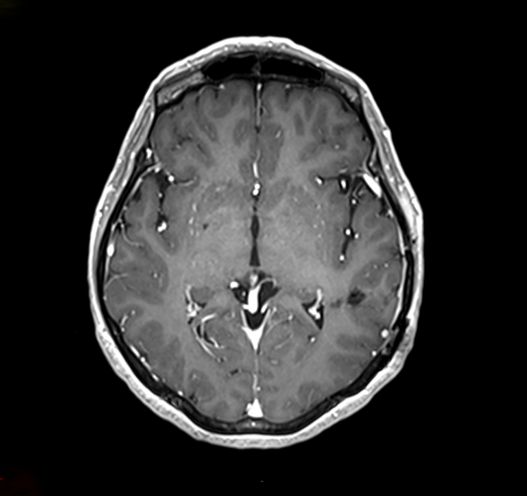

cavernome

Cavernome ayant saigné avant chirurgie

Le cavernome peut être visualisé sur un scanner cérébral mais l’examen de référence est l’IRM.